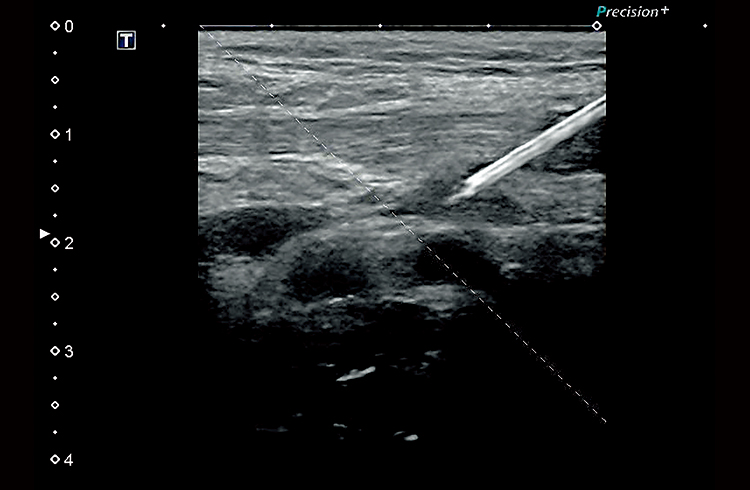

Технология улучшения визуализации биопсийной иглы BEAM, разработанная корпорацией Canon Medical Systems, в режиме реального времени обеспечивает четкое отображение кончиков игл на эхограмме.

Технология BEAM обеспечивает четкое отображение пункционных игл без необходимости выбирать оптимальный угол сканирования.